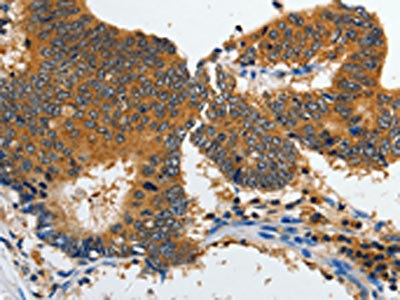

• The image on the left is immunohistochemistry of paraffin-embedded Human liver cancer tissue using CSB-PA788203(GRIA2 Antibody) at dilution 1/70, on the right is treated with synthetic peptide. (Original magnification: ×200)

• The image on the left is immunohistochemistry of paraffin-embedded Human colon cancer tissue using CSB-PA788203(GRIA2 Antibody) at dilution 1/70, on the right is treated with synthetic peptide. (Original magnification: ×200)